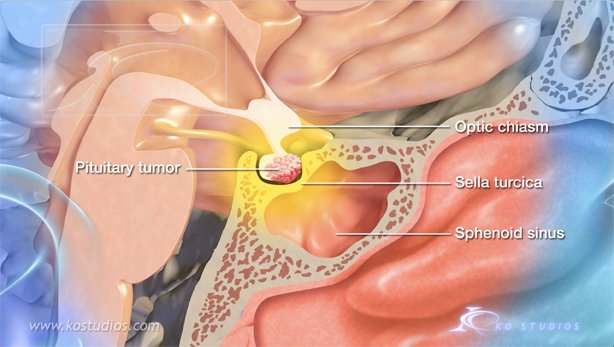

Endoscopic Pituitary Surgery-Nasal Approach

“A pituitary tumor is an abnormal growth of cells within or around the pituitary gland. Most pituitary tumors are non-cancerous growths called adenomas, which do not spread to other parts of the body. However, pituitary adenomas can cause the pituitary gland to produce too many or too few hormones, causing a variety of symptoms.”

This animations depicts tumor removal via the nasal approach.

Copyright©2021: BNI, Authors: KO Studios,

Narration: Dr. Andrew Little

https://www.barrowneuro.org/condition/pituitary-tumors/